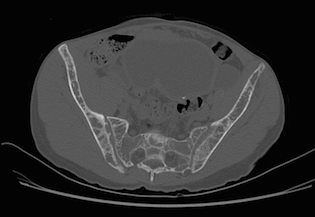

Alteração difusa do trabeculado ósseo em toda a região avaliada, associada a focos de reabsorção óssea subcondral na sínfise púbica e na borda anterior das sacroilíacas, relacionados à doença de base (hiperparatireoidismo).

Associam-se sinais de fratura patológica no colo do fêmur esquerdo, com reabsorção óssea junto ao foco de fratura e desalinhamento entre os fragmentos, com sinais de derrame articular do quadril homolateral, de aspecto reacional.